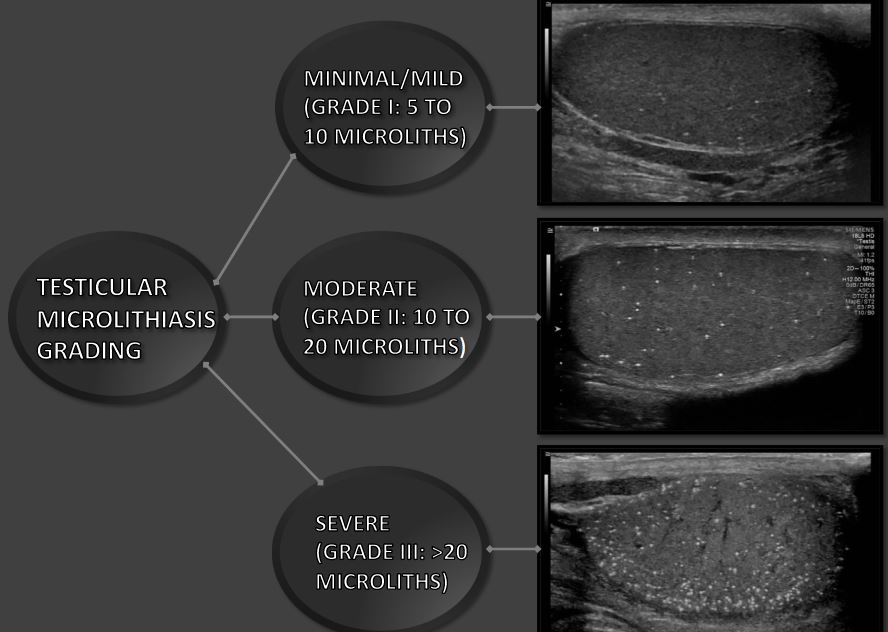

반짝이는 인공물은 평가할 때 볼 고환 미세 결석 컬러 도플러 초음파. 마이크로리스의 수 이미징에서 감지된 내용은 다를 수 있습니다. 상당히. 조건 로 등급이 매겨졌다 최소/약함(등급 I: 5~10 microliths), 중간 (등급 II: 10 내지 20 마이크로리스), 및 중증(등급 III: >20 마이크로리스)에 따라 미세 석회화 수 단일 보기에서 볼 수 있습니다.